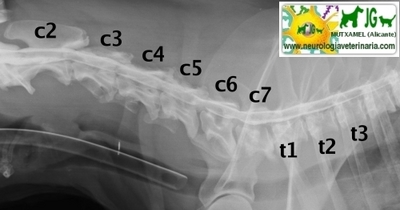

MIELOGRAFIA con inyección de contraste en la cisterna magna |